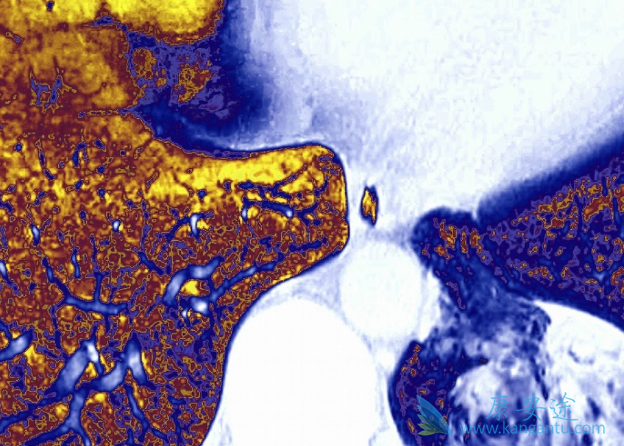

泰瑞莎(AZD9291)在国内和国外都做了临床实验,与国外的临床实验相比,泰瑞莎在国内临床实验的结果和国外的临床实验结果一样,只要存在T790M突变的,效果是一样的。这里就要指出一个问题,患者不要“盲吃”,因为“盲吃”是非常危险的。我们知道所有的肺癌病人尤其是腺癌病人中,60%存在突变,但其它类型的突变相对比较低。如果耐药后不做检测,自己去盲吃,有一半的可能是无效的,是会出问题的。